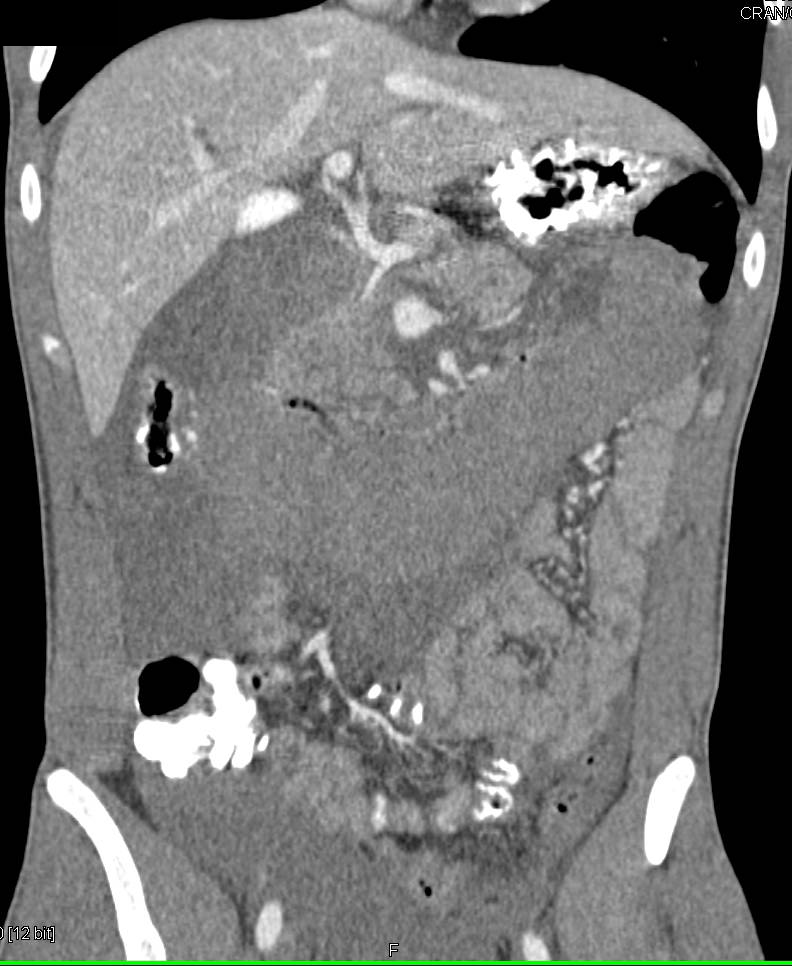

Pancreatic Cancer Invades the 4th Portion of the Duodenum and Causes Obstruction